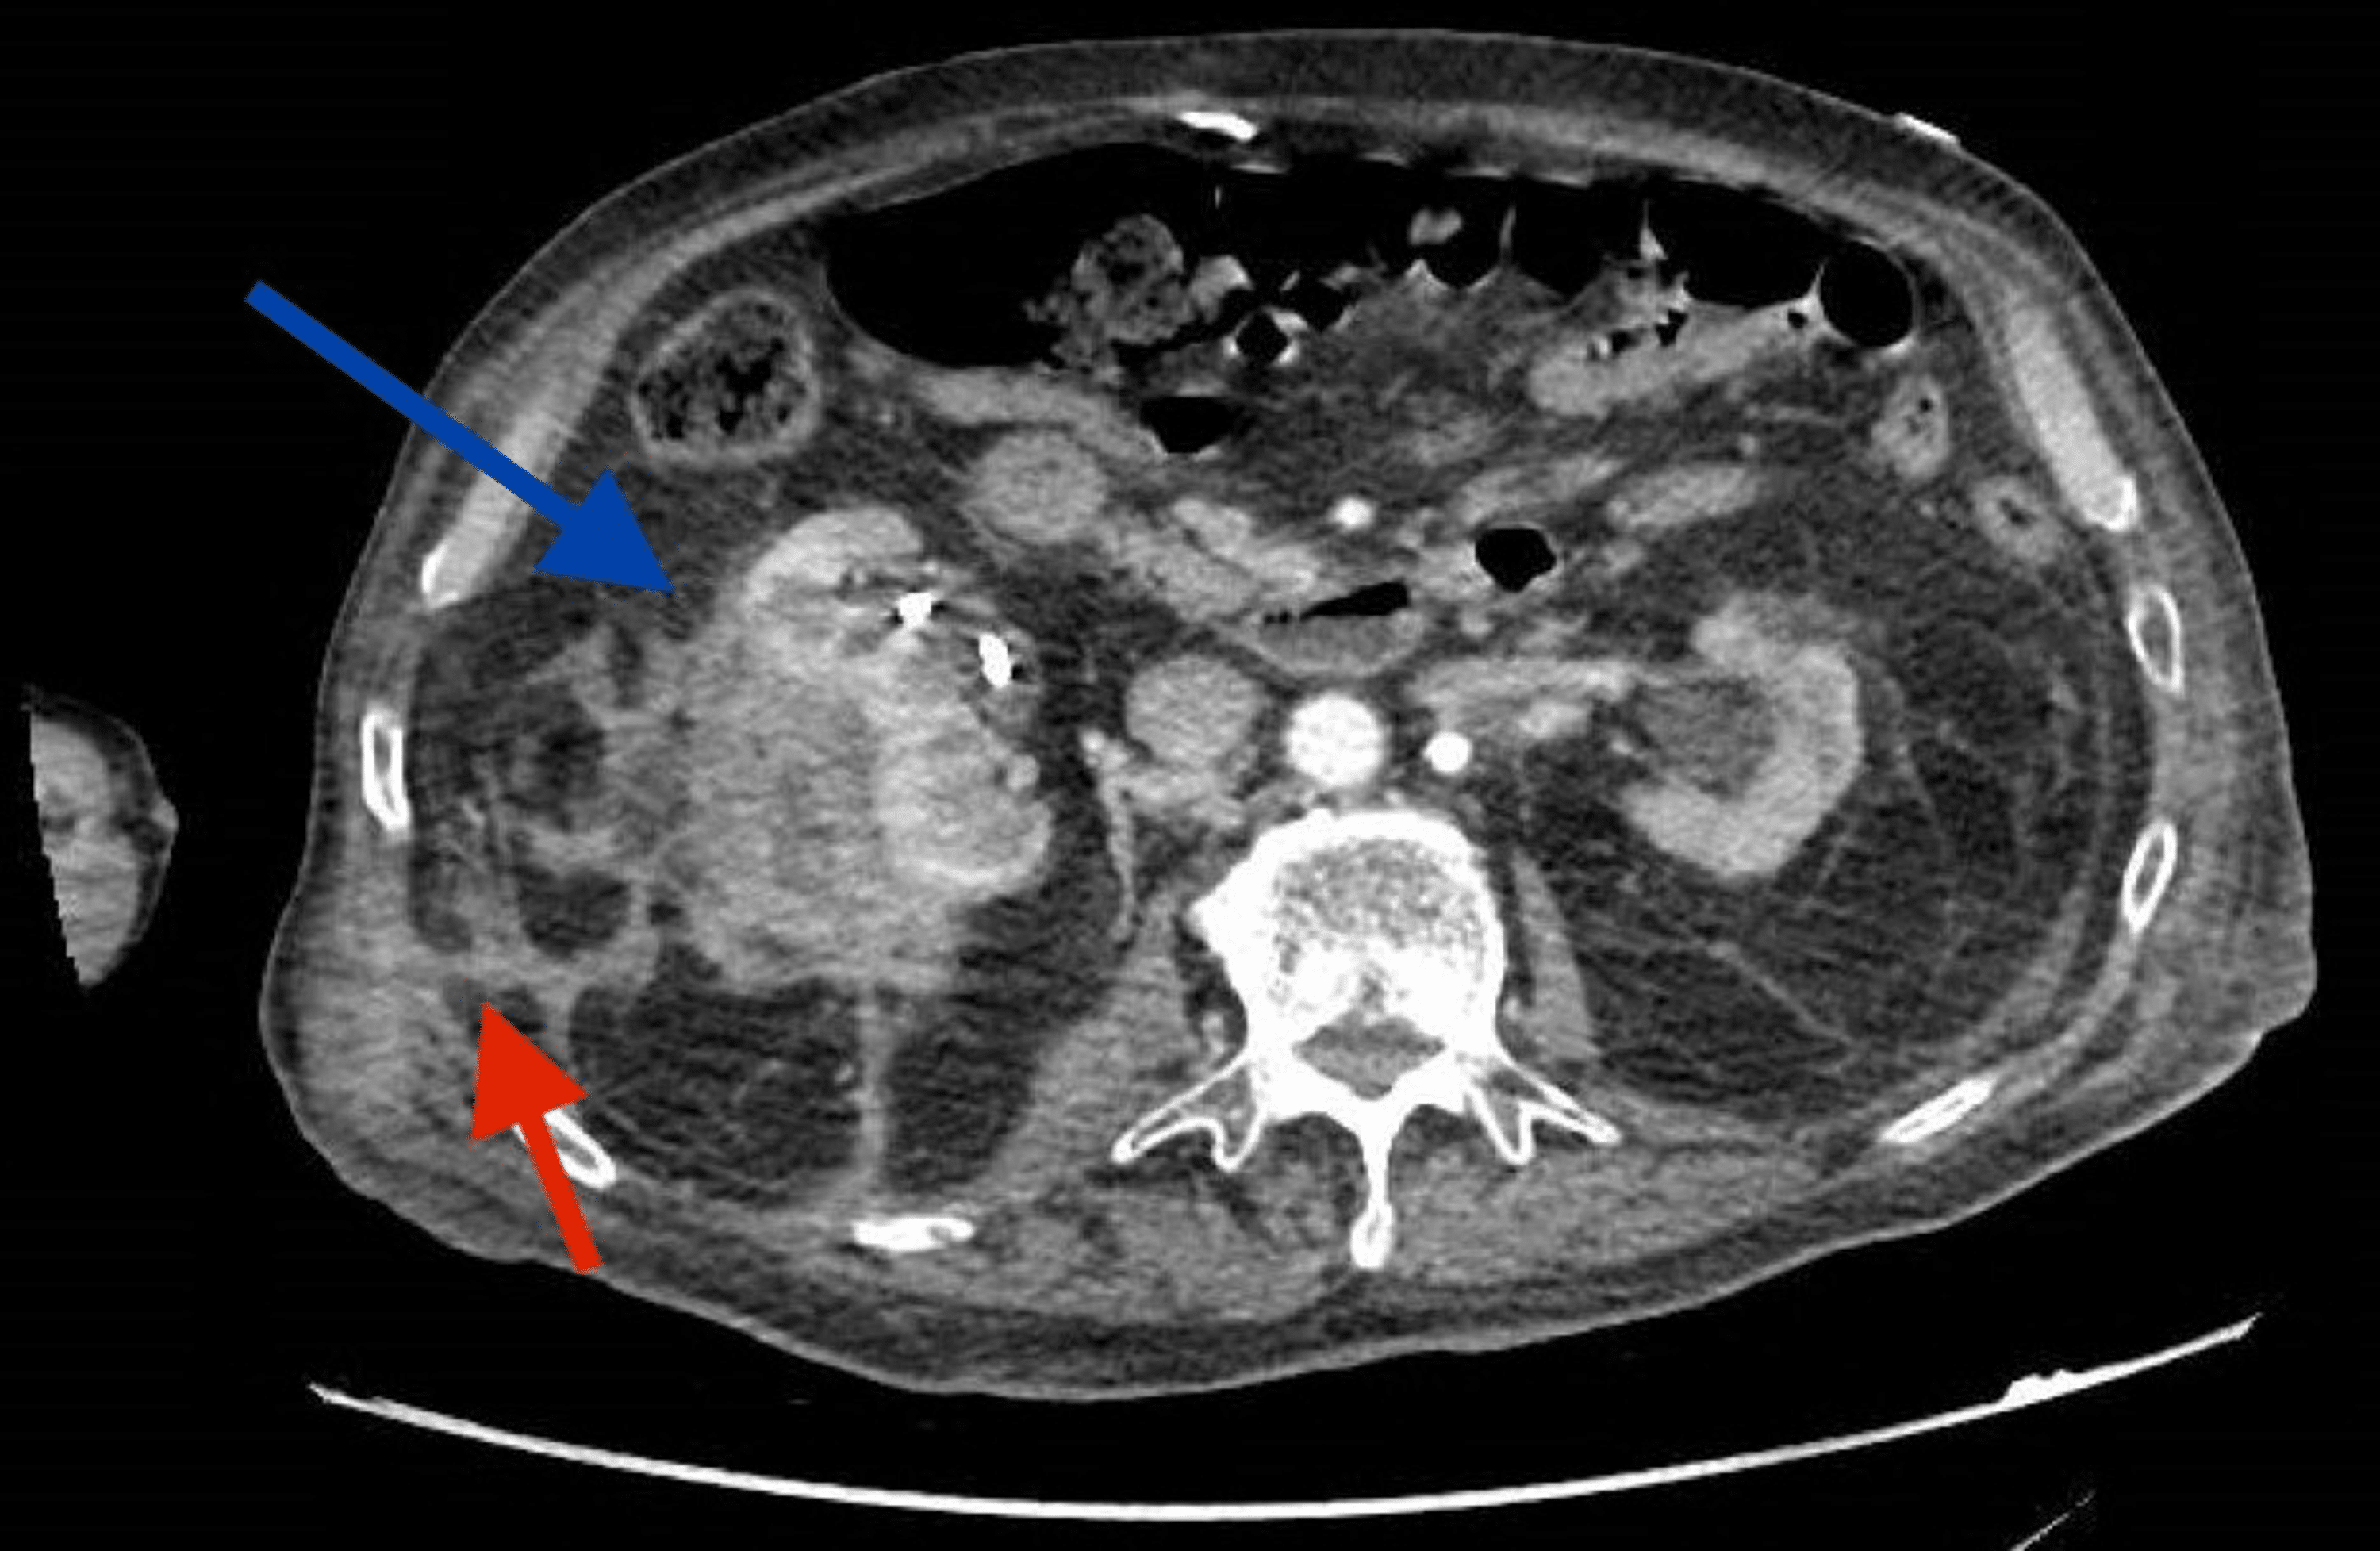

Renal abscesses Radiology Cases Periosteal Abscess Radiology orbital cellulitis represents a group of conditions ranging from periorbital inflammation to subperiosteal and orbital. patterns of periosteal reaction, both in morphology and distribution, are key to distinguishing benign or physiologic periosteal reaction from. Pediatric rhabdomyosarcoma of the orbit ; subperiosteal orbital abscess. intravenous contrast allows ct to differentiate between different tissue types and characterize abscesses. Periosteal Abscess Radiology.